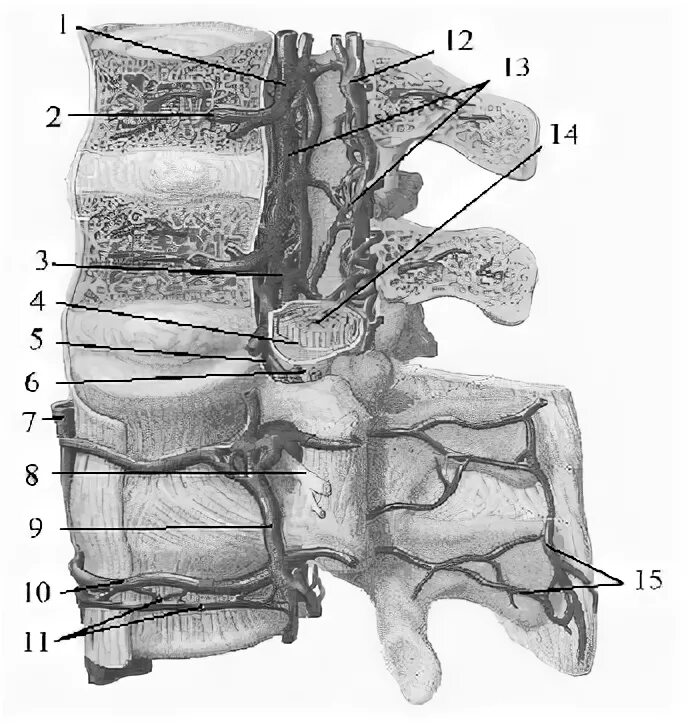

Компрессия дурального мешка что это